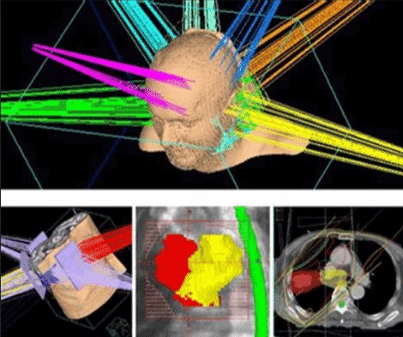

三維適形放療(3DCRT)

利用多葉光柵或適形擋鉛技術(shù),將照射野的形狀由普通放療的方形或矩形調(diào)整為腫瘤的形狀,從而使照射的高劑量區(qū)在人體內(nèi)的三維立體空間上與腫瘤的實(shí)際形狀相一致。三維適形放療提高了腫瘤的照射劑量,保護(hù)了腫瘤周圍的正常組織,降低了放射性并發(fā)癥,提高腫瘤的控制率。

與常規(guī)放療相比,3DCRT對(duì)腫瘤組織的適形聚焦照射和對(duì)正常組織的良好保護(hù),提高了腫瘤與正常組織的計(jì)量比。在正常組織受到允許劑量照射的情況下,腫瘤組織可以得到比常規(guī)放療更高的總劑量。治療時(shí)可以明顯地提高單次劑量,縮短總的治療時(shí)間??梢愿行У乇Wo(hù)正常組織,降低放射損傷,提高腫瘤的局部控制率。

適形放療是根據(jù)腫瘤的立體大小,從三維方向上,采用多野、多角度進(jìn)行照射,而且每個(gè)照射野的截面形狀與對(duì)應(yīng)的腫瘤形狀相一致。靶區(qū)形狀雖已適形,但靶區(qū)內(nèi)劑量分布欠均勻。